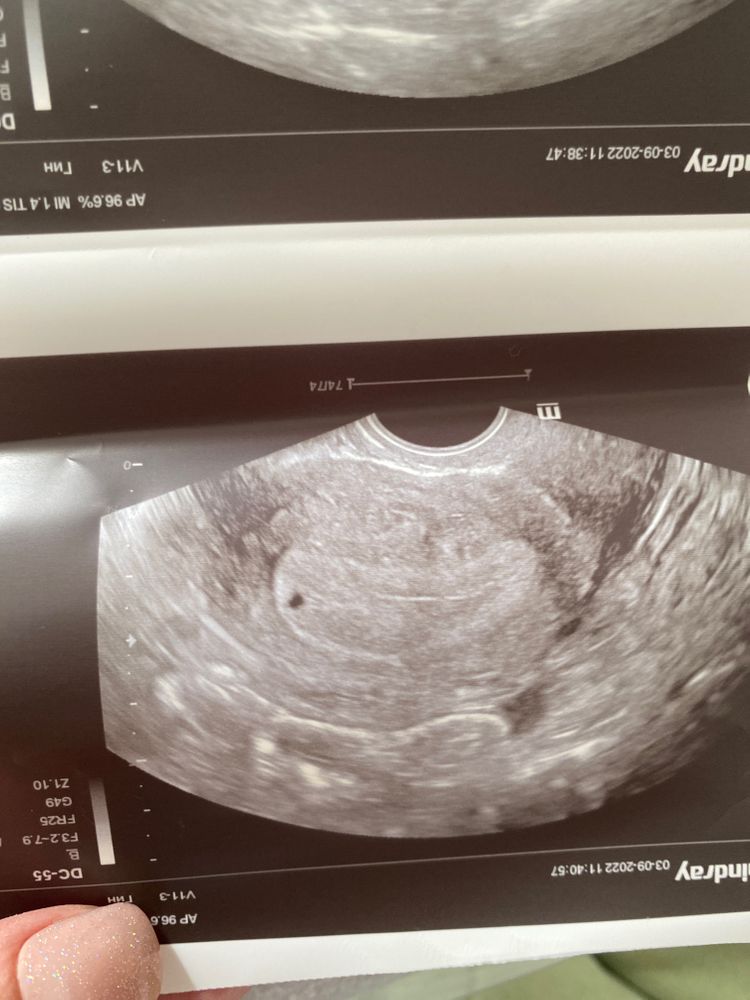

В декабре прошлого года была внематочная беременность, удалили вместе с правой трубой, сейчас тест положительный. Видно ли тут что нибудь? Очень переживаю

Сейчас плодное яйцо очень маленькое, поэтому врач УЗИ не уверен. Все решит повторное УЗИ через 10 дней и анализ ХГЧ количественно

Сикирина Ольга, спасибо большое! Но вот эта точка, это вроде как пя? Или нет?

Юлия Маркотнова, повторяю, при таком крошечном размере нельзя 100% гарантировать , что это плодное яйцо, надо, чтобы оно подросло, надо дождаться результатов ХГЧ.